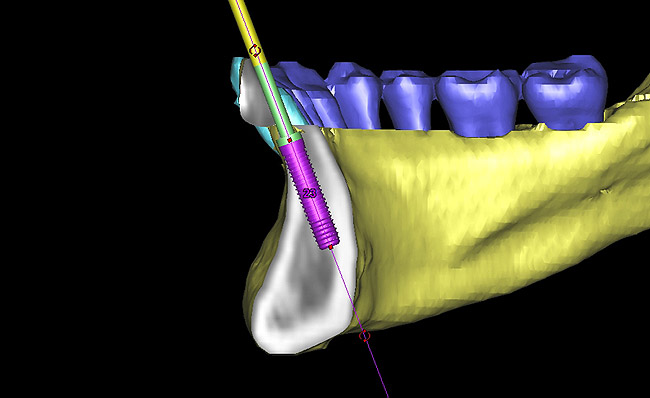

Figure 15  Presurgical 3-dimensional CT scan diagnostic planning for implant No. 23. Note the anticipated dehiscence at the facial aspect of the implant.

Figure 15

Figure 16  A cross-sectional view of postorthodontic site development at No. 23 position. Sufficient bone has been developed to accommodate implant placement in an optimal prosthetic position. Simultaneous GBR is planned at the coronal most portion of the implant per anticipated dehiscence.

Figure 16

Following the first goal of orthodontia—moving tooth No. 22 to a proper functional and anatomical position—a periodontal reevaluation was performed, demonstrating an improvement in short- and long-term tooth prognosis. At this time, the decision was made to abort continual extrusion of teeth Nos. 21 and 22, although some attachment level discrepancy remained between Nos. 21 and 22 (Figure 14). Implant diagnostics ensued and included mounted study models and a diagnostic wax-up. A scanning appliance was created to demonstrate the desired prosthetic outcome requirements, and the patient was referred for computed tomography (CT) scans. CT scan assessment demonstrated successful orthodontically directed GBR to allow implant placement (Figure 15 through Figure 16). Only minor GBR therapy would be needed and could be accomplished simultaneously with implant installation. Guided implant placement occurred, using an open flap approach (Figure 17). During surgery, root dehiscences were noted on teeth Nos. 21, 22, 24, and 25, as well as the anticipated dehiscence following implant placement at No. 23 (Figure 18). A positioning reference (index) was secured after implant placement to facilitate a provisional prosthesis at stage II surgery. Cortical perforations then were placed adjacent to the implant to encourage angiogenesis (Figure 18), and mineralized freeze-dried bone allograft enhanced with platelet-derived growth factor was placed over the dehiscences for purposes of guided tissue regeneration and GBR (Figure 19). A highly resorbable collagen membrane was placed to stabilize the allograft. The flap was coronally repositioned, and primary-intention wound healing was achieved (Figure 20 and Figure 21). Following 4 months of stage I surgery, implant uncovery and immediate provisionalization were performed in conjunction with connective tissue grafting. Final orthodontic tooth movement then ensued, using the implant as anchorage to optimize end-tooth movements, interroot separation, and the cuspid-protected occlusal scheme. A final impression then was secured, and a zirconia abutment (Figure 22) with an all-ceramic restoration was fabricated for the prosthetic phase completion of No. 23 (Figure 23 through Figure 25).